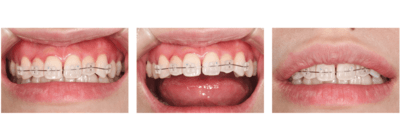

治療中

矯正装置をつけています。だんだん八重歯が動いてきているのがわかります。今回のケースでは、抜歯を行わずに矯正ができました。